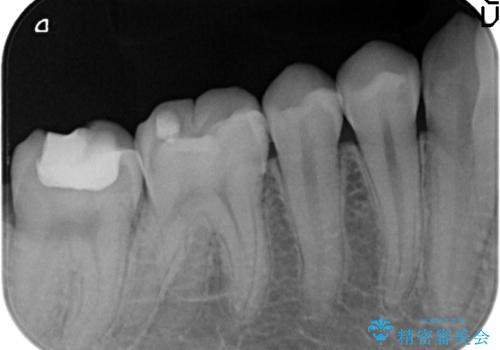

- 右下4、5番目の銀歯を白くしたいといらっしゃった方の症例です。

銀歯を除去後、セラミックインレーによる修復を行いました。

当院のセラミックインレーはemaxという強度と審美性に優れた材料を使用しています。

またプレス方式でインレーを製作しているため、削り出しで製作するCADCAMより優れた適合性も持ち合わせており、虫歯が再発しにくい修復物です。